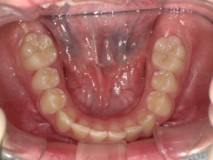

Before

After

【小学生】マイオブレース矯正 上顎前突(出っ歯)と叢生(でこぼこ)を改善

治療期間

2年

治療開始

8歳

種類

マイオブレース矯正

使用装置

機能矯正装置 咬合斜面版

現在は終了後8年たっていますが、今も定期健診にきてくれて 歯並びを保っています